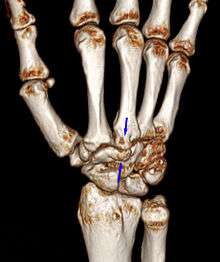

Carpal boss VR-3D-Reconstruction

Carpometacarpal bossing (or metacarpal/carpal bossing is a small, immovable mass of bone on the back of the wrist. The mass occurs in one of the joints between the carpus and metacarpus of the hand, called the carpometacarpal joints, where a small immovable protuberance[1] occurs when this joint becomes swollen or bossed.

The joint between the index metacarpal and the capitate is a fibrous non-mobile joint. Some people have a gene that leads to this growth. It looks like arthritis (bone spurs on each side of the joint) on X-ray. It looks like a ganglion on the hand, but more towards the fingertips.